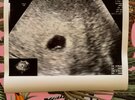

Dziewczyny jestem po wizycie, wszystko jest ok. Jest pęcherzyk ciążowy 7,6mm♥️

Termin porodu jednak na 17.02, także poproszę o zmianę na liście, kolejna wizyta 30.06 😊

Bóle brzucha mogą być winą powiększonych jajników jeszcze po punkcji. Także jestem spokojniejsza 😊

• IMG_9231.jpeg

IMG_9231.jpeg

181,6 KB · Wyświetleń: 75